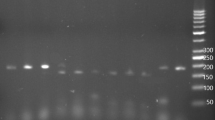

Based on the multiplex PCR with mismatch primers, the three PON polymorphisms could be identified simultaneously. The multiplex PCR amplification yielded products of 111 bp for PON1-192, 144 bp for PON1-55, and 196 bp for PON2-311. After incubation with HinfI, the presence of PON1-192R resulted in digestion of the 111 bp product into fragments of 77 and 34 bp, and the presence of PON1-55L resulted in digestion of the 144 bp product into fragments of 122 and 22 bp. The 196 bp product of PON2-311 was digested into 173 and 23 bp in the presence of the S allele. For PON2-148, the 232 bp product was digested into 161 and 71 bp in the presence of the A allele (Fig. 1).

Separation of (a) PON multiplex PCR products after digestion with HinfI by 4 % agarose gel electrophoresis. The combined genotypes (PON1-192, PON1-55, PON2-311) resulting from the analysis are (left to right) QQ-LM-CC; QR-MM-CS; RR-MM-CS; QQ-LL-SS. Separation of (b) single PCR products relative to the PON2-148 polymorphism after digestion with Fnu4HI by 4 % agarose gel electrophoresis. Genotype analysis (left to right), AG (three bands of 232, 161, and 71 bp), PON2-148, AA (two bands of 161 and 71 bp). M, 25 bp DNA Step Ladder (Promega). Length of digestion products is reported on the left

The polymorphisms of Q192R and L55M were distributed at the PON1 locus, and the S311C and A148G polymorphisms at the PON2 locus (Table 2). All genotypes, at each locus, followed Hardy–Weinberg equilibrium, with all chi-square values <3.84 and p > 0.05. The prevalence of homozygous individuals for the PON1-55M allele was higher in the group without SCS. Carriers of the PON2-311C allele were significantly higher in the SCS group. No mutated genotype for the PON2-148 polymorphism was found in the two groups. No difference in allele frequency was observed between the two groups for any polymorphism.